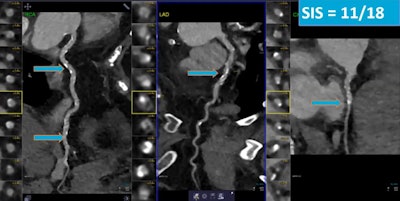

CCTA and SPECT myocardial perfusion imaging are established tests for evaluating ischemia and stenosis in patients with heart disease. CCTA-derived measures of plaque, such as segment involvement score (SIS), or the percentage of plaques in affected arteries, also independently predict severe events.

The researchers included 956 patients (54% men) with suspected CAD who had undergone CCTA and SPECT myocardial imaging at Houston Methodist between January 2016 and June 2020. The SIS was defined as the sum of segments with plaque, irrespective of the degree of stenosis, using an 18-segment coronary artery model. Patients were followed for major adverse cardiovascular events.

After a median follow-up of 31 months, 102 patients experienced a major event. An analysis showed SIS significantly predicted outcomes and improved risk discrimination in patients with CCTA obstructive stenosis (hazard ratio, 1.15) and SPECT ischemia (hazard ratio, 1.14). The CCTA hazard ratio was statistically significant, while the SPECT one was not.

"Plaque burden was associated with primary outcome, with hazard ratios showing each additional [SIS] segment added 15% increase in risk for incident events," Ahmed said.